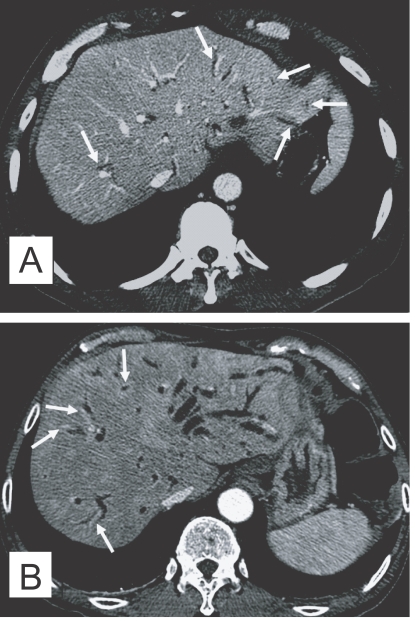

The principle imaging finding of clonorchiasis is diffuse dilatation of the peripheral intrahepatic bile ducts (Lim, 1990). However, the larger intrahepatic and extrahepatic bile ducts are not dilated or minimally dilated. The predominant dilatation of the peripheral intrahepatic ducts is due to the adult worms residing in the peripheral small bile ducts. Compared with normal subjects, many intrahepatic bile ducts are observed on cholangiography in patients with clonorchiasis due to the dilated peripheral intrahepatic bile ducts (Fig. 1A and B). Lim et al. (1992) reported "too many intrahepatic ducts" sign in 76% (22 of 29) of patients with clonorchiasis on direct cholangiography.

The presence of the fluke bodies in the peripheral bile ducts can be demonstrated on a cholangiogram (Choi et al., 1984; Lim et al., 1992). Cholangiography shows oval, elliptical, or filamentous, small filling defects within the dilated peripheral intrahepatic bile ducts, representing the flukes (Fig. 1) (Lim et al., 1992). It is a pathognomonic finding on direct cholangiography, but the defects can be obscured by the contrast medium. The filling defects by the flukes are usually small and irregular, with a uniform size on direct cholangiography, which are easily differentiated from stones (Fig. 1) (Choi et al., 1984; Lim et al., 1992; Jeong et al., 2004). Direct cholangiogram is obtained with an injection of iodine contrast material via catheter during either endoscopy or percutaneous biliary drainage (Fig. 1). Recently, non-invasive cholangiograms can be made by using MR imaging (Fig. 1) (Barish and Soto, 1997).

Fig. 1

Cholangiograms of clonorchiasis showing "too many intrahepatic ducts" signs. A. By percutaneous biliary drainage catheter (arrows) in a 58-year-old man, showing diffuse and uniform dilatation of the peripheral intrahepatic bile ducts. B. Endoscopic retrograde cholangiography in a 70-year-old man, with diffuse dilatation of the peripheral intrahepatic bile ducts, but no dilatation of the extrahepatic bile duct. C. Multiple, oval, small filling defects (arrows) within the dilated peripheral intrahepatic bile ducts, representing the flukes in a 55-year-old man. D. Magnetic resonance (MR) cholangiography in a 70-year-old man with diffuse dilatation of the peripheral intrahepatic bile ducts.

Fig. 1 Cholangiograms of clonorchiasis showing "too many intrahepatic ducts" signs. A. By percutaneous biliary drainage catheter (arrows) in a 58-year-old man, showing diffuse and uniform dilatation of the peripheral intrahepatic bile ducts. B. Endoscopic retrograde cholangiography in a 70-year-old man, with diffuse dilatation of the peripheral intrahepatic bile ducts, but no dilatation of the extrahepatic bile duct. C. Multiple, oval, small filling defects (arrows) within the dilated peripheral intrahepatic bile ducts, representing the flukes in a 55-year-old man. D. Magnetic resonance (MR) cholangiography in a 70-year-old man with diffuse dilatation of the peripheral intrahepatic bile ducts.